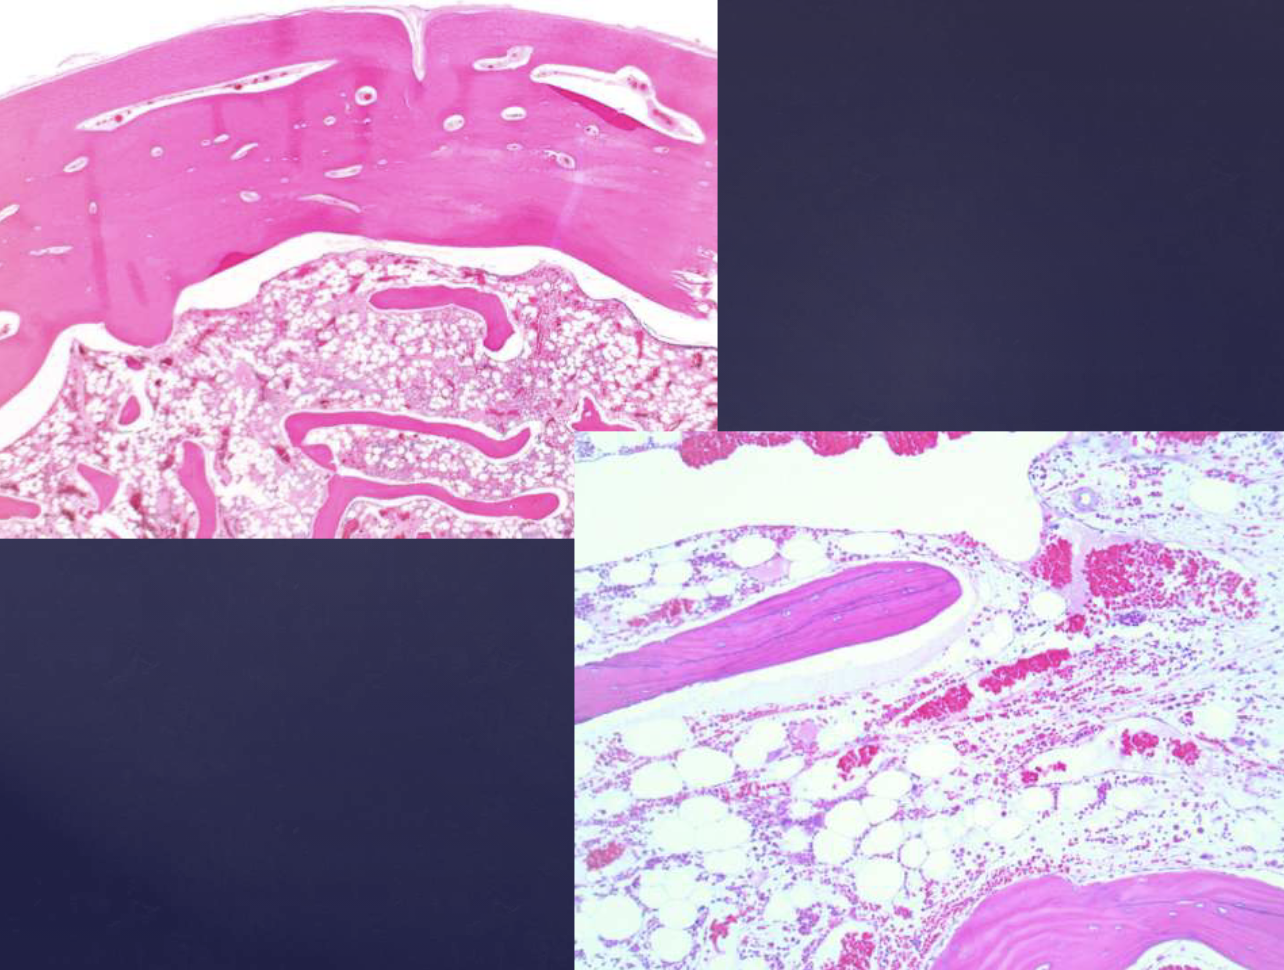

follicular pattern hisopath features of ameloblastomas

nests of epithelium

island centers resembling stellate reticulum

peripheral columnar cells with nuclei polarized opposite basement membrane (sub-nuclear vacuolization)

mature fibrous background

desmoplastic pattern hisopath features of ameloblastomas

compressed islands + cords of odontogenic epithelium in densely collagenized stroma, presents in anterior max